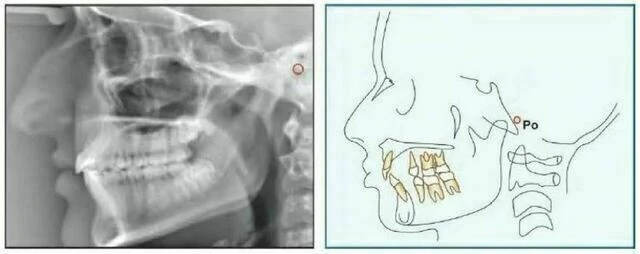

Porion (Po) Đỉnh của ống tai ngoài. Đôi khi do khó xác định porion nên sử dụng đỉnh của bóng thanh tai, điểm này được gọi là “machine porion”